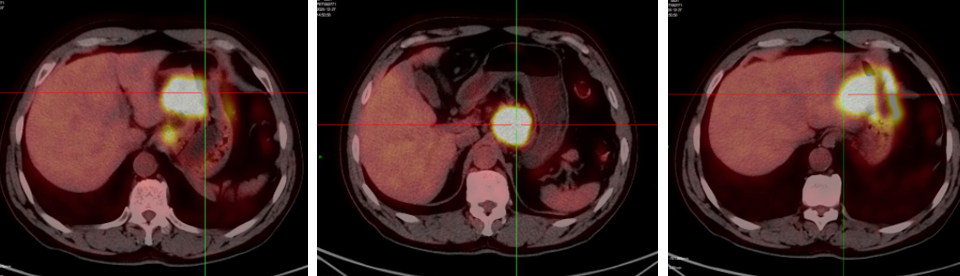

• PET-CT(2024年12月26日):①胃体多处不规则增厚伴FDG代谢增高,恶性考虑,胃癌符合;②肝胃间隙、胃小弯侧多发肿大淋巴结,FDG代谢增高,转移考虑,累及肝左叶及胰腺可能;③胃周、大网膜多发小结节,不伴FDG代谢增高,转移待排,建议密切随访(图4)。

图片4.png图4. PET-CT检查(2024年12月26日)